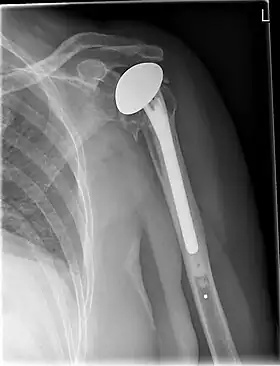

X-ray of a shoulder prosthesis

Various materials can be used to make prostheses, however the majority consist of a metal ball that rotates within a polyethylene (plastic) socket. The metal ball takes the place of the patient's humeral head and is anchored via a stem, which is inserted down the shaft of the humerus. The plastic socket is placed over the patient's glenoid and is typically secured to the surrounding bone via cement.[11]